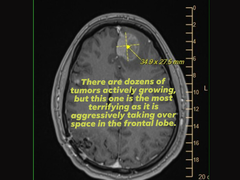

For proof, she also attached an image of a brain scan (MRI) that showed an aggressive tumor of the frontal lobe while pleading for support or help from executives at Epic Games, who made the key decisions regarding the layoffs.